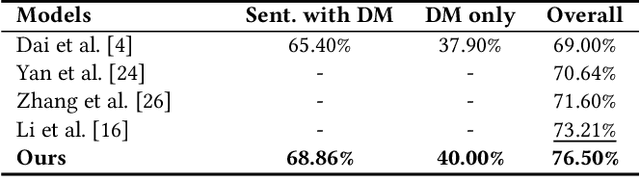

Extracting meaningful drug-related information chunks, such as adverse drug events (ADE), is crucial for preventing morbidity and saving many lives. Most ADEs are reported via an unstructured conversation with the medical context, so applying a general entity recognition approach is not sufficient enough. In this paper, we propose a new multi-aspect cross-integration framework for drug entity/event detection by capturing and aligning different context/language/knowledge properties from drug-related documents. We first construct multi-aspect encoders to describe semantic, syntactic, and medical document contextual information by conducting those slot tagging tasks, main drug entity/event detection, part-of-speech tagging, and general medical named entity recognition. Then, each encoder conducts cross-integration with other contextual information in three ways: the key-value cross, attention cross, and feedforward cross, so the multi-encoders are integrated in depth. Our model outperforms all SOTA on two widely used tasks, flat entity detection and discontinuous event extraction.